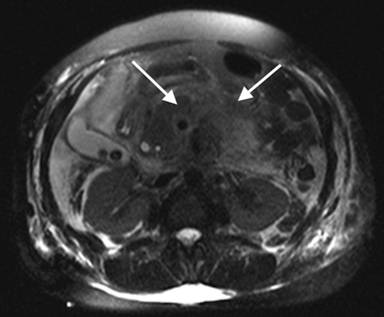

Our patient is a72-year-old woman who initially presented to an outside hospital in January 2011 with severe epigastric abdominal pain and near syncopal episode. Initial diagnostic tests revealed elevated amylase, lipase and transaminase levels. An abdominal computed tomography (CT) scan showed a diffusely edematous pancreas with peripancreatic inflammation. She was treated conservatively with bowel rest and appropriate fluid resuscitation. Once stable, she underwent magnetic retrograde cholangiopancreatography (MRCP), which indicated an intraluminal filling defect in the conjoined portion of the common bile duct and pancreatic duct near the ampulla suspicious for stone, clot or tumor (Figures 1 and 2), in addition to the marked pancreatic edema and peripancreatic inflammation (Figure 3). The patient then underwent endoscopic retrograde cholangiopancreatography (ERCP), which confirmed a lesion in the ampulla of Vater. This lesion was biopsied and thereby only partially resected. Additionally, a pancreatic stone was discovered and removed. The patient received biliary sphincterotomy and stent placement. The final pathology of the biopsy specimen revealed duodenal papillary adenoma with high-grade dysplasia. The patient convalesced from this acute episode and was discharged with planned follow-up to discuss the treatment strategy for the ampullary lesion.

Figure 3. Axial MRCP image demonstrating significant pancreatic edema and peripancreatic inflammation (white arrows). |